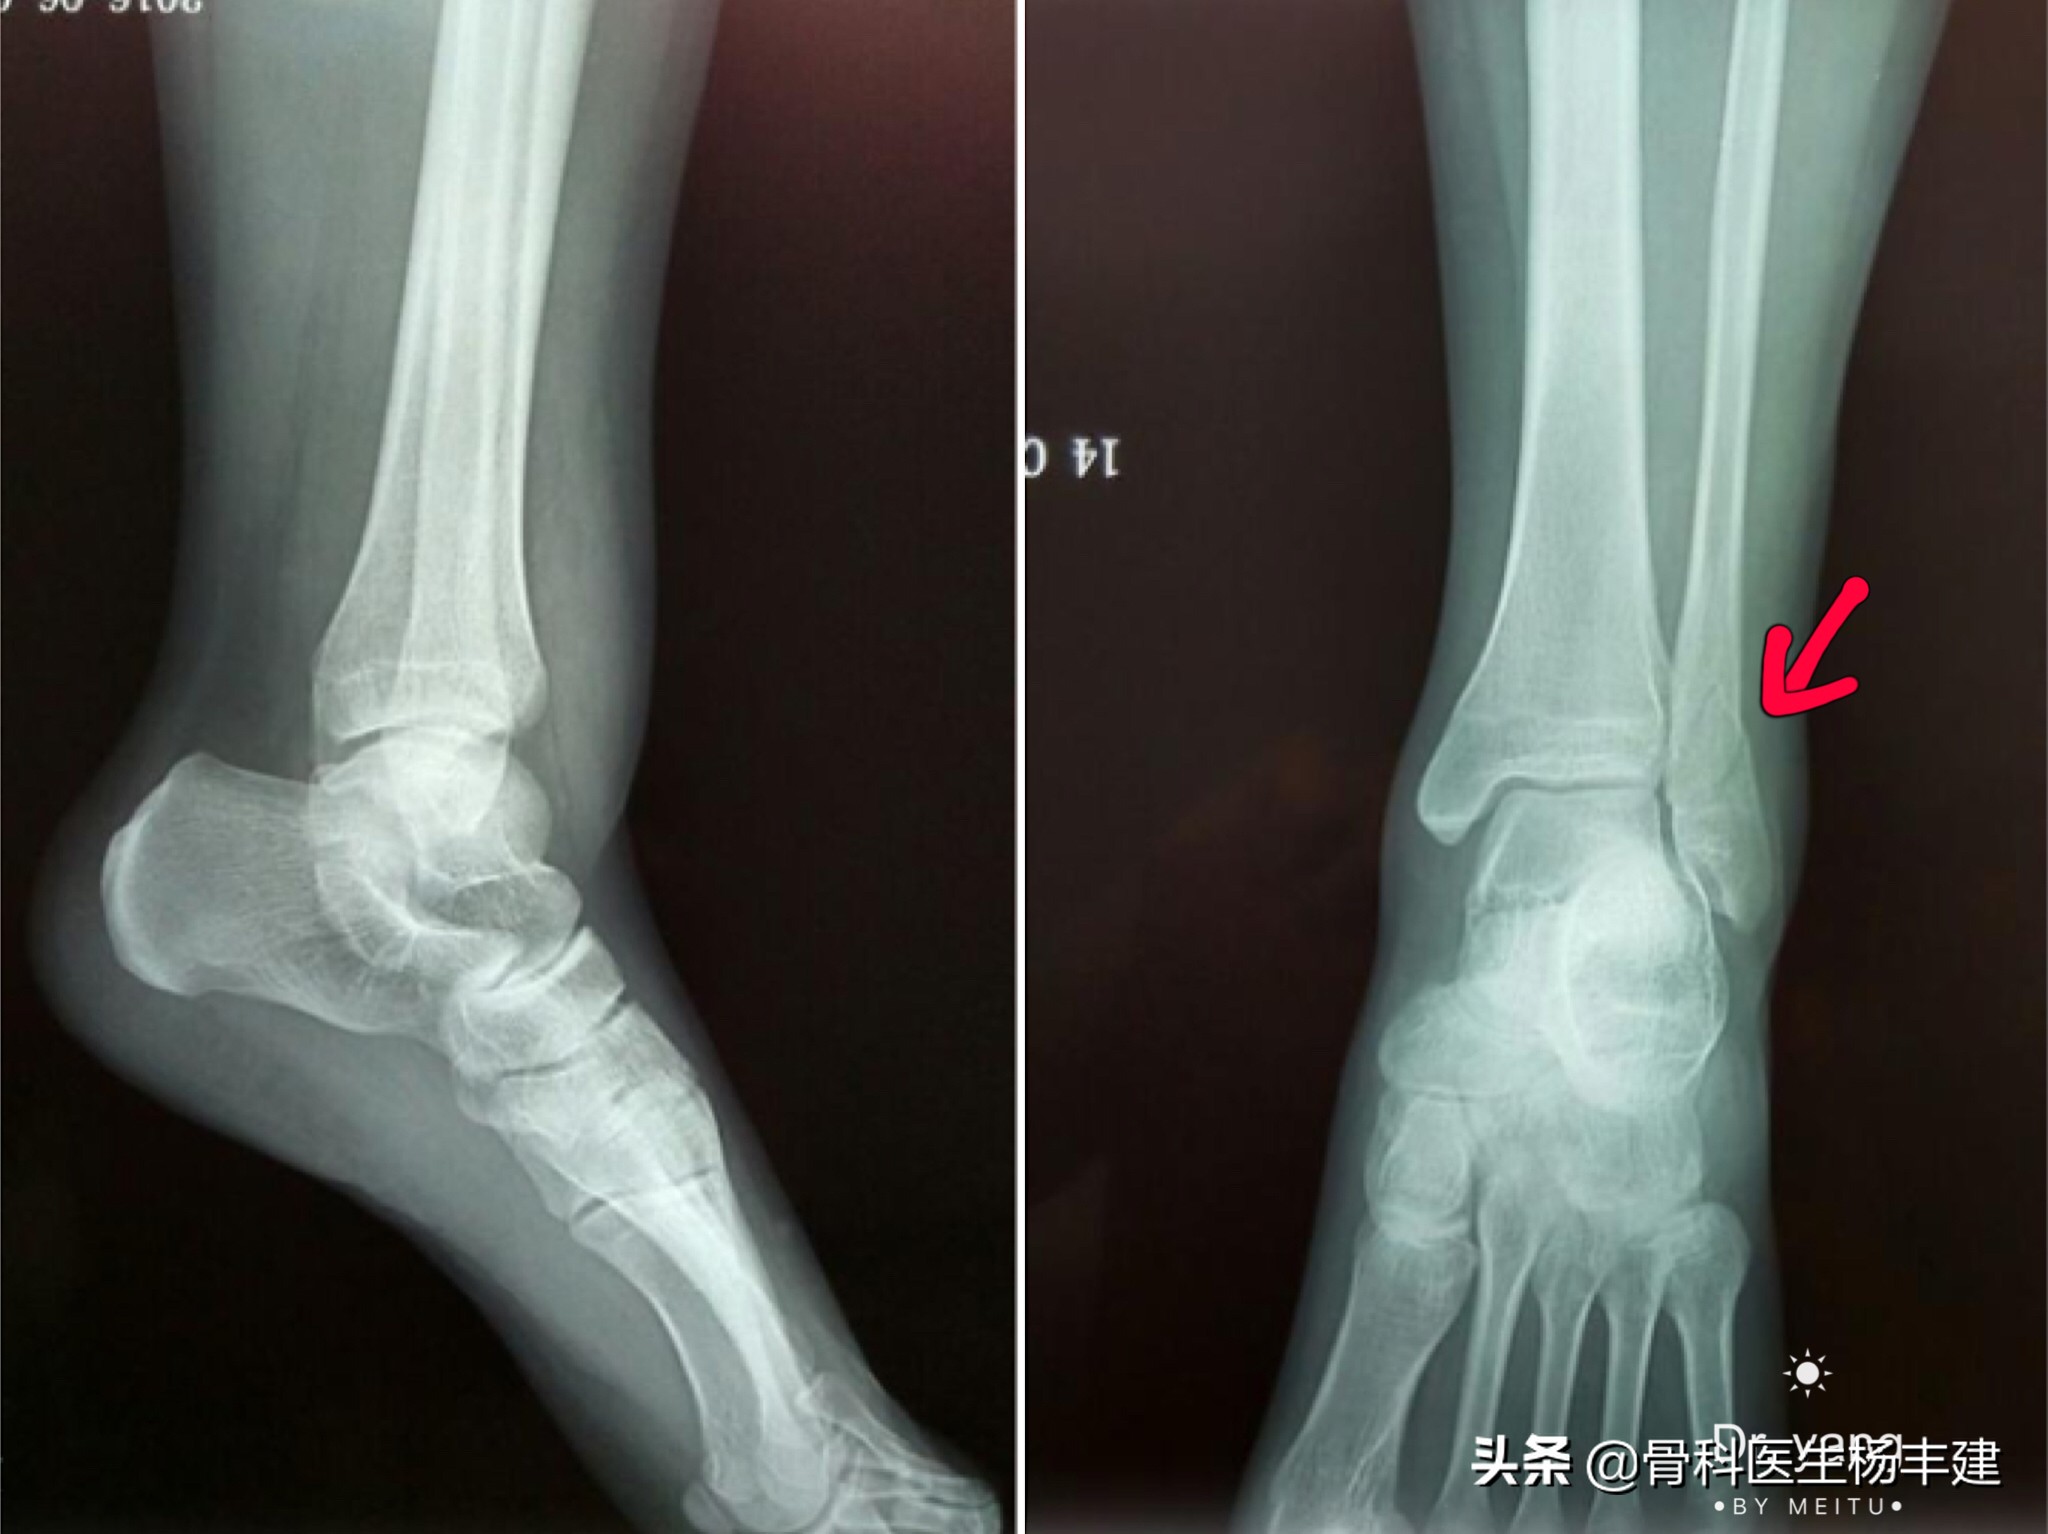

3,那么什么样的骨折需要做手术呢?如果损伤造成了两处,甚至两处以上的骨折(比如说内踝、外踝同时骨折,甚至连同后踝一起骨折),踝关节的稳定性往往会遭到破坏,从而出现比较明显的移位,这种情况是需要做手术治疗的。

内外踝均有骨折,并有明显移位,是手术治疗的指征

②骨折复位后,还需要关节下胫腓联合的宽度,以及踝穴两侧关节间隙的宽度。如果出现骨折完全复位,但是两侧关节间隙的宽度不对称,说明距骨的位置有问题,很可能存在下胫腓联合的脱位,也是需要修正的,通常使用螺丝钉收紧下胫腓联合。

手术前可见内侧踝穴明显增宽,距骨向外侧移位。手术中使用长螺钉收紧下胫腓联合,推挤距骨归位。